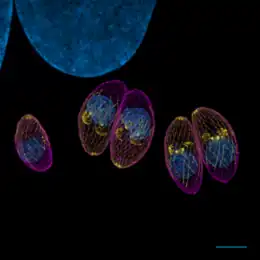

- le stade tachyzoïte, forme proliférative infectieuse chez l’hôte intermédiaire, se développe dans des vacuoles transitoires qui peuvent contenir jusqu’à 128 parasites ; cette forme peut se retrouver aussi chez le fœtus.

- Il se reproduit rapidement par un processus de multiplication asexuée (endodyogénie) chez l’hôte intermédiaire, toujours dans des macrophages. Puis il en sort en perforant la paroi au moyen d’une protéine qu’il produit (perforine). Des parasites génétiquement modifiés pour ne pas produire cette protéine ne peuvent sortir du macrophage qui gonfle en formant une boule[17]. Visuellement, l’enveloppe du parasite a la forme d’une goutte d’eau un peu arquée (toxon en grec signifie « arc »), d’environ 6 à 8 μm de longueur et de 3 à 4 μm de largeur. Le pôle postérieur arrondi contient le noyau tandis que le pôle antérieur plus aigu possède des ultrastructures adaptées à la pénétration cellulaire (complexe apical).

Le , l'Institute for Advanced Biosciences révèle dans la revue Cell Host & Microbe sa découverte du mécanisme déployé par le parasite toxoplasma gondii afin de rentrer dans une cellule. Le parasite injecte dans la membrane plasmique d'une cellule, un complexe de protéines capable de former une porte par laquelle il s'engouffre. Toxoplasma gondii va alors pouvoir s'isoler dans la vacuole ainsi créée en faisant une rotation sur lui même qui provoque l'obturation du sas d'entrée. Le parasite peut alors se développer à l'abri[21].